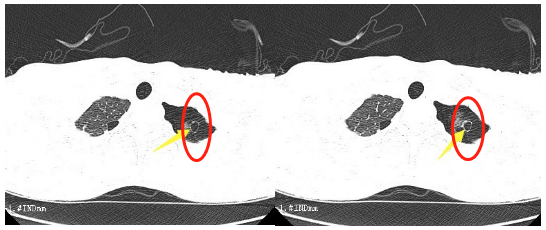

我院成功开展全区首例Nd︰YAG激光治疗气道病变 一根细长的光纤,似一把锋利的光剑,将病魔击倒。日前,我院呼吸与危重症医学科上演了这么一幕酷似《星球大战》的画面。 近日,我院刘碧翠副院长及呼吸与危重症医学科团队成功为两名患者实施经支气管镜Nd∶YAG激光消融术,并取得了良好的效果。 该项技术为我区首次开展,呼吸与危重症医学科运用新科技的力量不断增加、完善治疗手段,为广大患者带来了福音。 患者唐先生,68岁,因“反复咳嗽1年,呼吸困难1周”来我院诊疗,曾在我院呼吸与危重症医学科明确诊断为肺鳞癌 ⅣA期,诊断明确后,先后行化疗及PD-1单抗免疫治疗。一周前,唐先生出现呼吸困难加重再次来我院就诊,在为该患者行支气管镜检查后,发现其气管下端新生物堵塞管腔约90%,左主支气管完全堵塞。呼吸与危重症医学科结合病人体征特点,并与患者家属进行充分沟通后,于1月16日对唐先生进行电子支气管镜介入Nd∶YAG激光消融术治疗,并结合圈套器、氩气刀、冷冻切除等技术。最终,堵塞气管及左主支气管的肿瘤被清除,管腔明显通畅,患者呼吸困难症状消失。 患者黄女士,40岁,来我院就诊后被诊治为“支气管结核”,给予电子支气管镜介入治疗时见右上叶支气管开口肉芽肿完全堵塞管腔,经Nd∶YAG激光消融后,肉芽肿消失,手术取得良好效果。 “激光”最早在20世纪初由爱因斯坦发现,它被人类称为“最快的刀”、“最准的尺”、“最亮的光”。经过数年发展,激光被广泛应用在各项领域,其中便包括临床医学。Nd︰YAG激光治疗是激光医学领域的一项新技术,原理是Nd︰YAG(掺钕钇铝石榴石)激光沿着可弯曲的石英纤维经过支气管镜操作孔到达病变组织,使局部组织的温度迅速达到200~1000℃,从而凝固坏死、碳化甚至汽化,达到清除的目的。其具有能量高度集中、组织穿透性强、能准确地定位于病变部位的特点,同时还具有止血的效果。并且,Nd︰YAG激光治疗的价格更为低廉,极大地减轻了患者负担。 目前,该项技术主要用于气道内阻塞性病变以及各种原因引起的气道狭窄,包括气道良性肿瘤、恶性肿瘤、结核性肉芽肿、瘢痕狭窄等。这项新技术的开展为气道良、恶性狭窄患者的治疗提供了新的方向,填补了我区该技术领域的空白。 我院呼吸与危重症医学科成立于1998年,现有业务用房3820㎡,开放普通病床130张(含RCC床位6张),设有住院病区、门诊、门诊综合诊疗室、支气管镜室、胸腔镜室、肺功能室、睡眠监测室,是重庆市第一批特色专科、第一批市级重点专科、第一批区级重点专科,2020年通过国家PCCM达标评审。 科室目前开展了经无创(有创)呼吸机辅助通气、皮肺穿刺活检术、支气管镜常规检查术、内科胸腔镜检查术、难治性气胸的自体血或碘伏胸腔内注入治疗术、支气管镜下透壁肺活检、经支气管镜纵隔淋巴结穿刺术、支气管镜下球囊扩张术、支气管镜下冷冻冻切冻融术、支气管镜下圈套电刀氩气刀切除肿瘤术、支气管镜下Nd︰YAG激光消融术、支气管镜下支架植入术、大容量全肺灌洗术、支气管动脉栓塞治疗大咯血、支气管舒张试验、支气管激发试验、FeNO检测、肺癌基因检查与分子靶向治疗及免疫治疗等先进诊疗技术,造福广大患者。